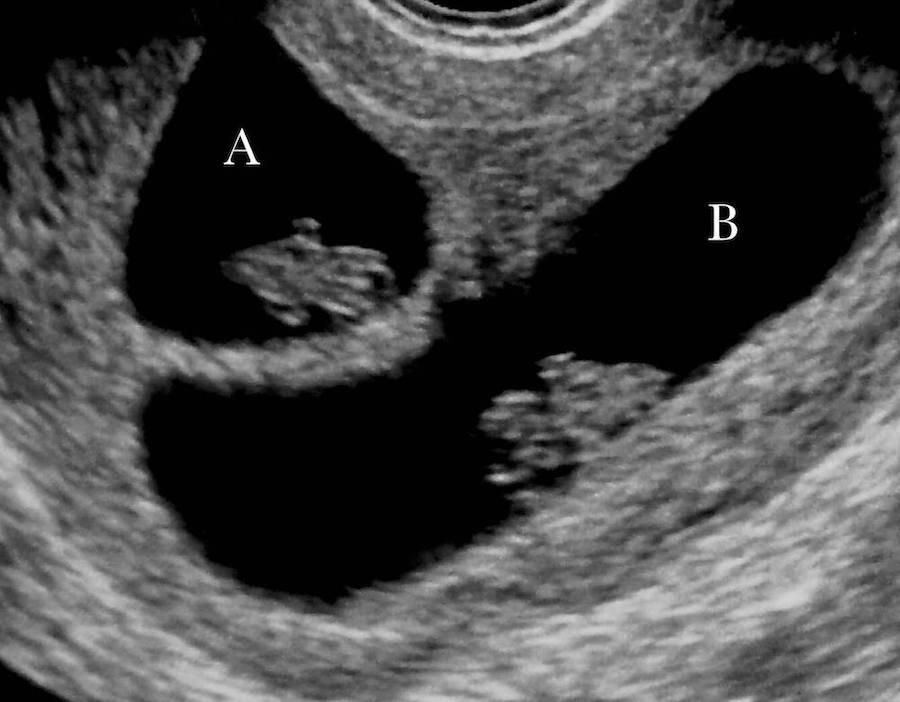

Follows a twin pregnancy in the First Trimester and shows you your baby's changes so you learn what you can expect to see during your own st Trimester sonogram, including how we measure and date your pregnancy.